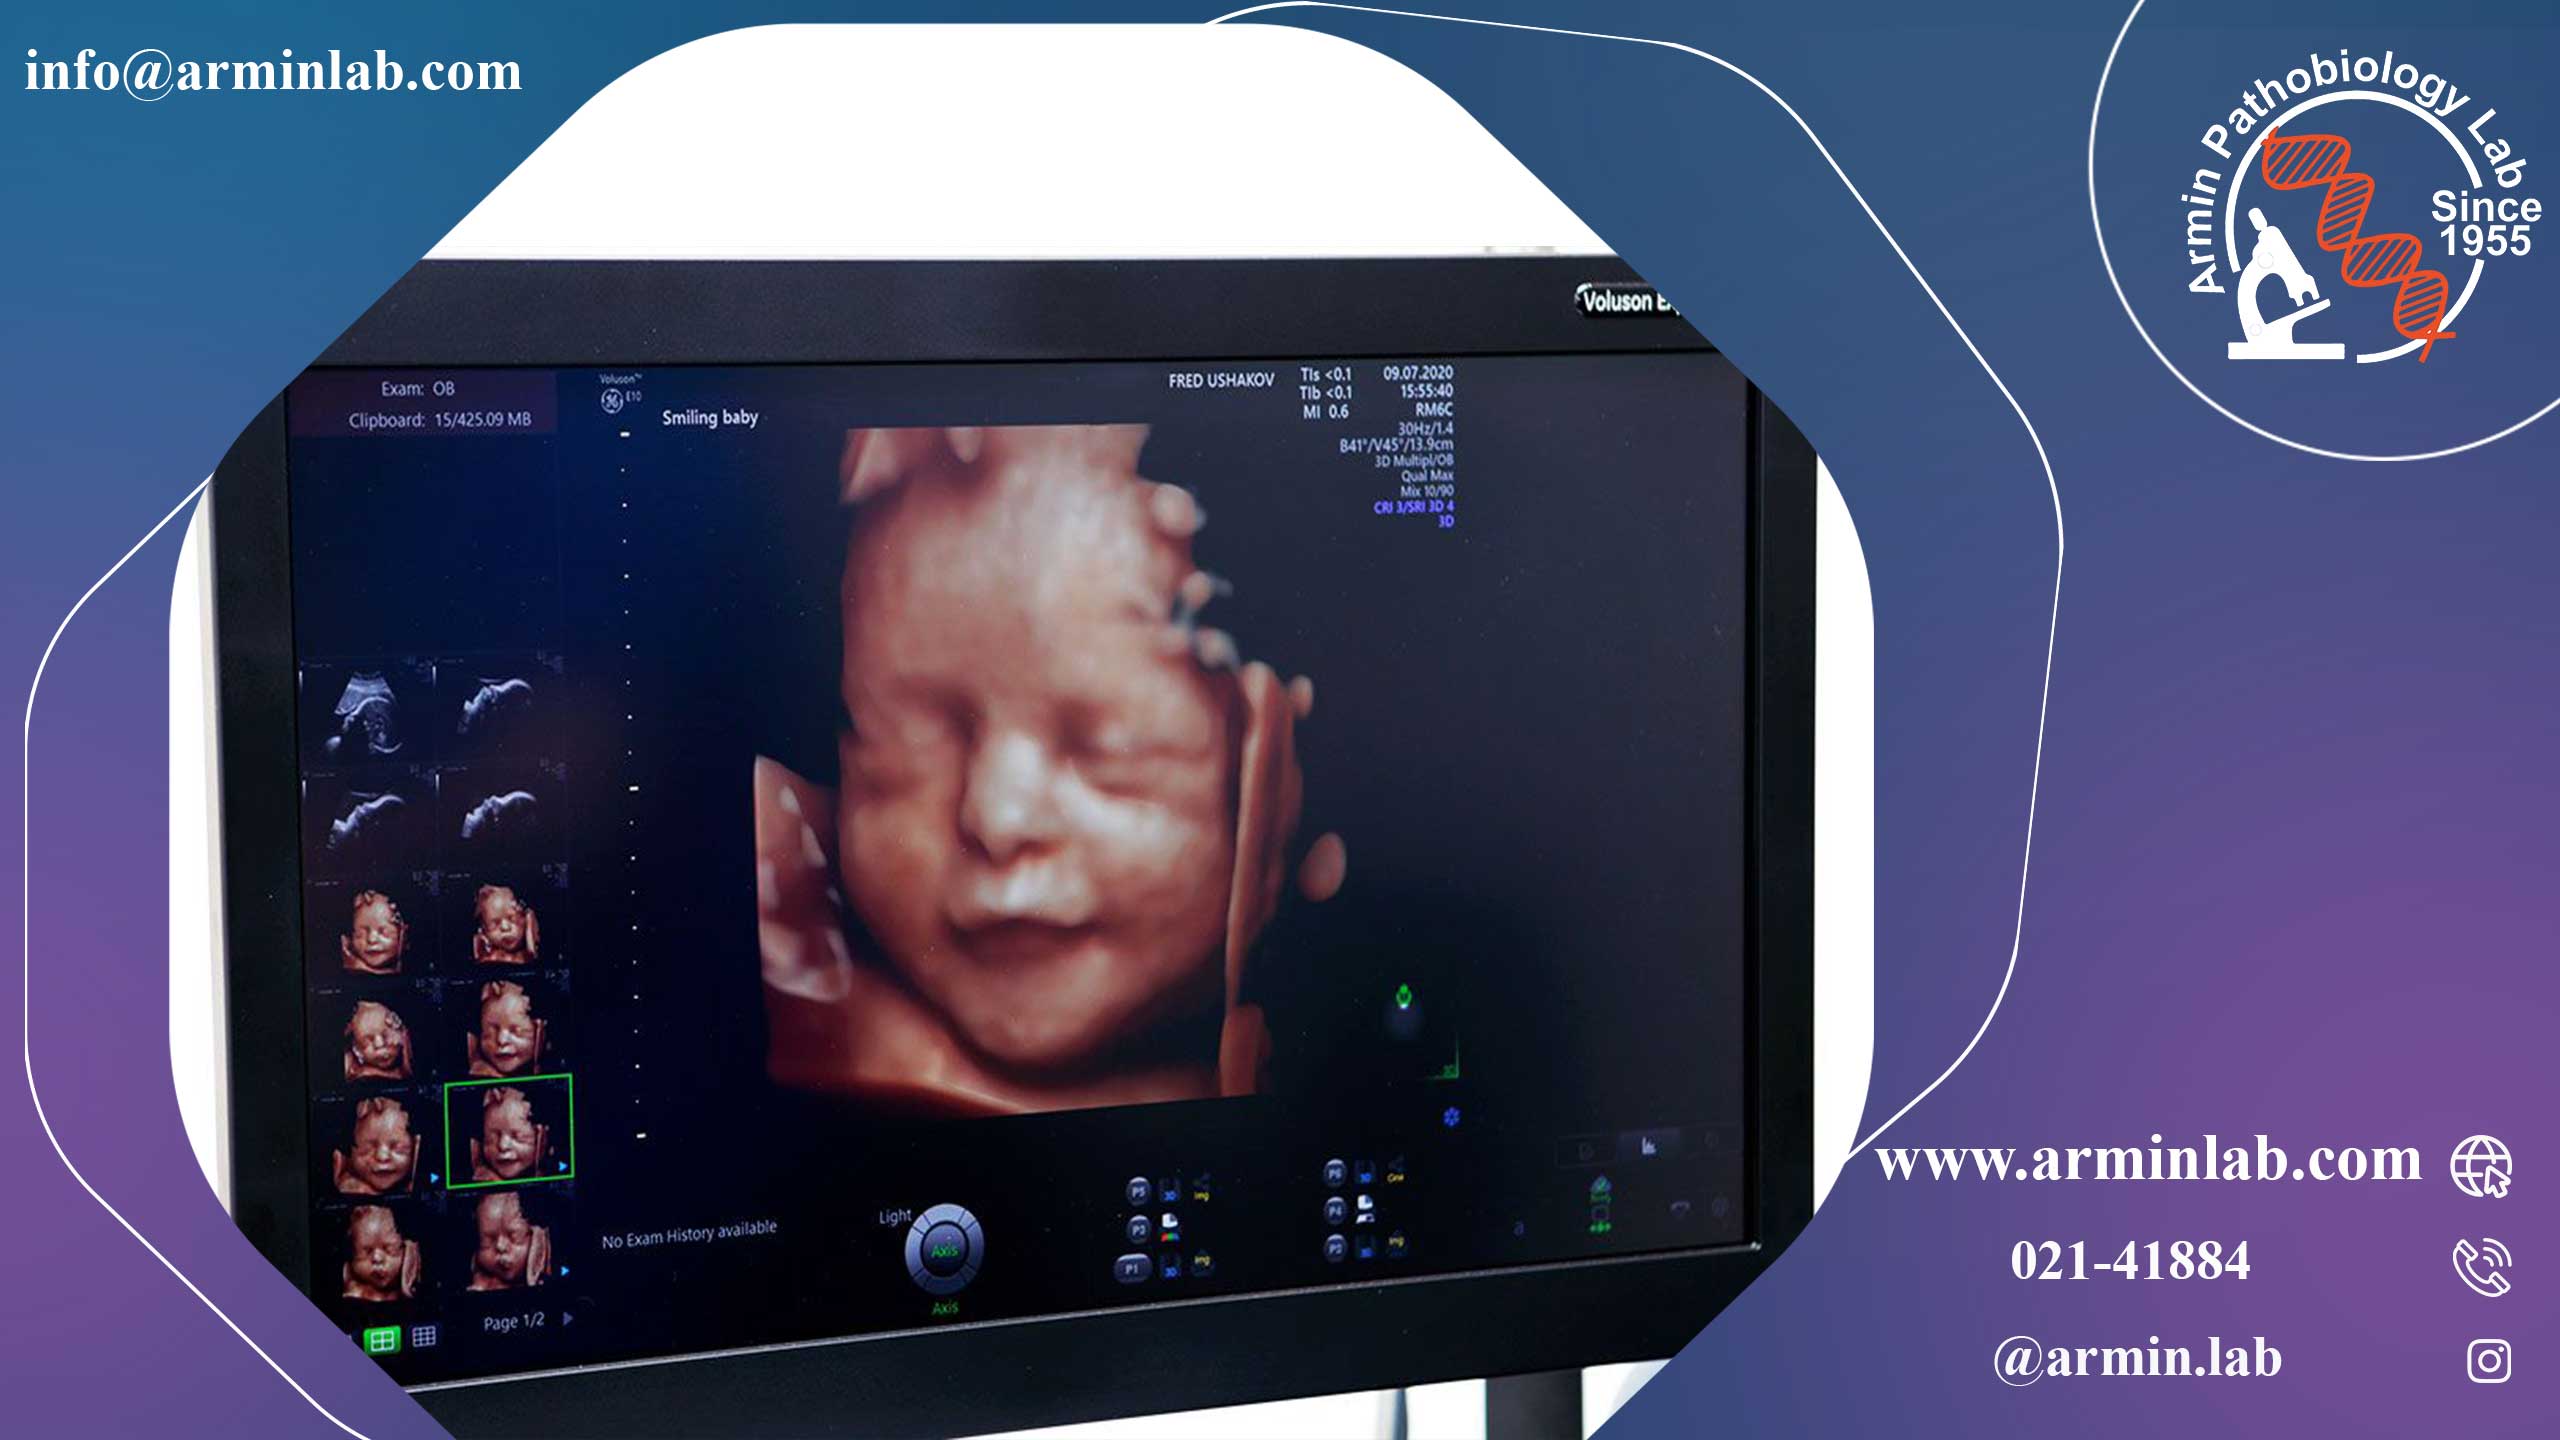

سونوگرافی ۲۰ هفتهای که گاهی سونوگرافی آنومالی نیز نامیده میشود، حدود هفته ۱۸ تا ۲۲ بارداری انجام میشود. این سونوگرافی رشد اندامها و قسمتهای بدن جنین را بررسی میکند و میتواند برخی از بیماریهای مادرزادی را تشخیص دهد. در بیشتر موارد، میتوانید جنسیت جنین را نیز تشخیص دهید.

بیشتر زنان این اسکن را یک مرحله هیجانانگیز میدانند، زیرا اغلب اولین دید واضح از کودکشان را فراهم میکند.

سونوگرافی از امواج صوتی برای تهیه تصاویری از داخل بدن استفاده میکند. تکنسین دستگاهی به نام مبدل را روی شکم حرکت میدهد تا تصاویر مورد نیاز خود را از جنین بگیرد. آنها همچنین اندازهگیریهای خاصی انجام میدهند و اندامها و قسمتهای بدن را بررسی میکنند. پزشک شما از تصاویر برای بررسی نحوه رشد جنین و بررسی مشکلات احتمالی سلامتی استفاده میکند.